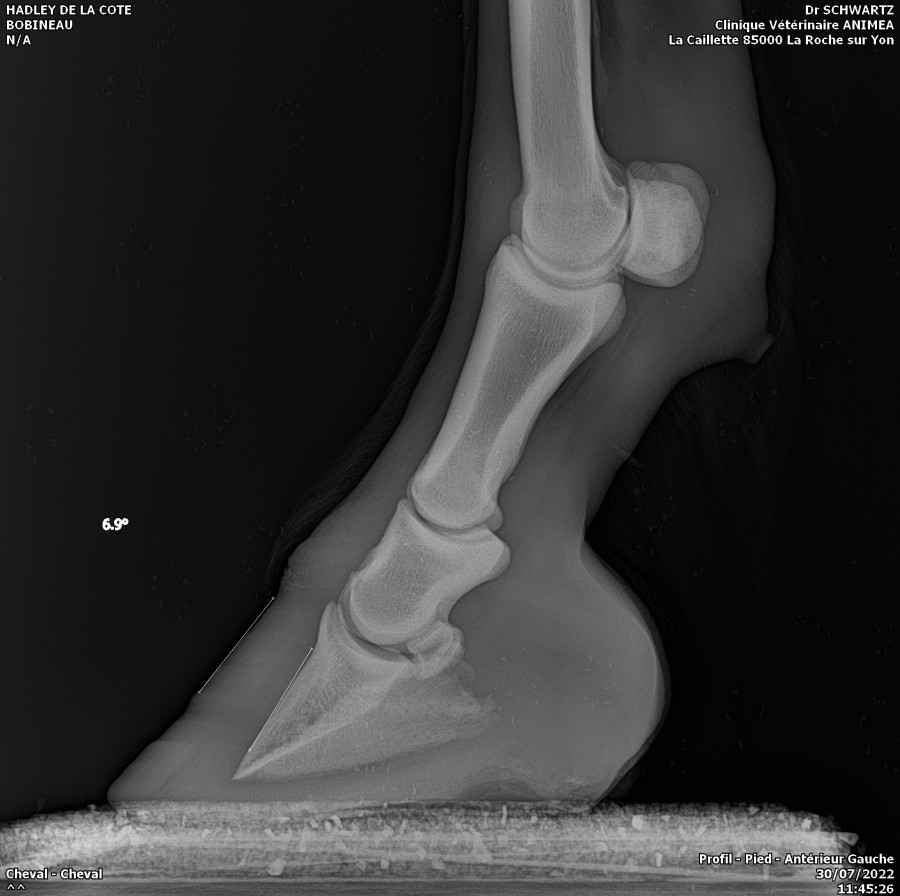

Hadley va bien mieux. Débourrage terminé et sa fourbure qui régresse bien. Les antérieurs sont maintenant ok avec 0 et 1 degrés d'inclinaison. Les postérieurs encore a travailler par le maréchal car il reste 4 et 7 degrés de basculement encore.

Comparaison maintenant/avant

hisatis39 je ne savais pas non plus avant que cela lui arrive. La veto avait preconisé des fers mais conjointement avec le marechal ont a decider de faire sans. C'est plus facile car il faut parer toutes les 3 semaines. idealement, il aurait fallu que je passe un coup de rappe toute les semaines mais avec mon accident aux cotes, je ne pouvais pas. En gros il faut couper en pince, les parois et descendre les talons mais ne pas toucher á la sol qui est fine. La, on a bien recuperer en sol.

Je pense poster sur Facebook en partage publique car on reconnait tous une fourbure des antérieurs mais pas des postérieurs. le cheval est campé dans ce cas. si je n'avais pas insister pour des radios, ..... le pire de tout cela c'est que lorsque j’étais allé la premier fois pour des radios des rotules, le veto avait préconiser de laisser des tallons hauts. sur ceux j'avais demander si cela ne pouvait pas engendrer un basculement des 3eme phalanges. On m'a presque rit au nez. que ce n’était pas vraiment probable sur des postérieurs. Comme quoi, il faut parfois suivre son instinct et non rester sur la théorie..... Bref, le pauvre, cela ne l'a pas aidé!